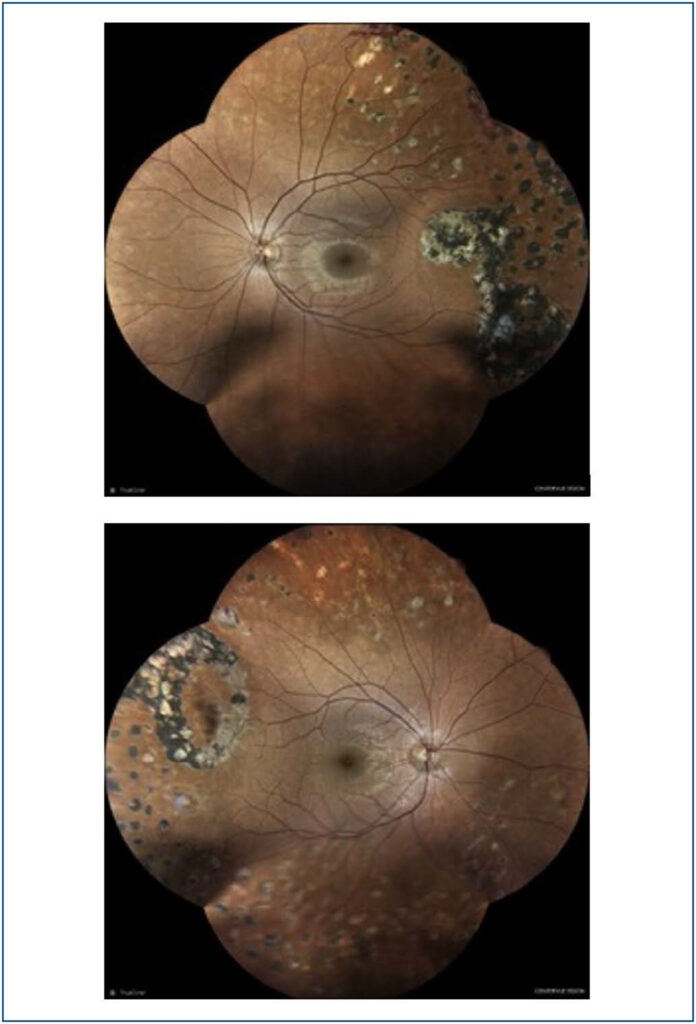

Clínica e tratamento de doença de Eales no Nordeste do Brasil

A doença de Eales é uma vasculopatia idiopática oclusiva periférica caracterizada por inflamação, isquemia e vascularização retiniana. Afeta principalmente jovens saudáveis e frequentemente é bilateral. O diagnostico é clínico, entretanto, requer exclusão de outras doenças sistêmicas, infecciosas e oculares. A hemorragia vítrea recorrente é sua apresentação principal. O prognostico visual é bom, se tratado precocemente. Reportamos aqui uma série de casos diagnosticados no Nordeste do Brasil.